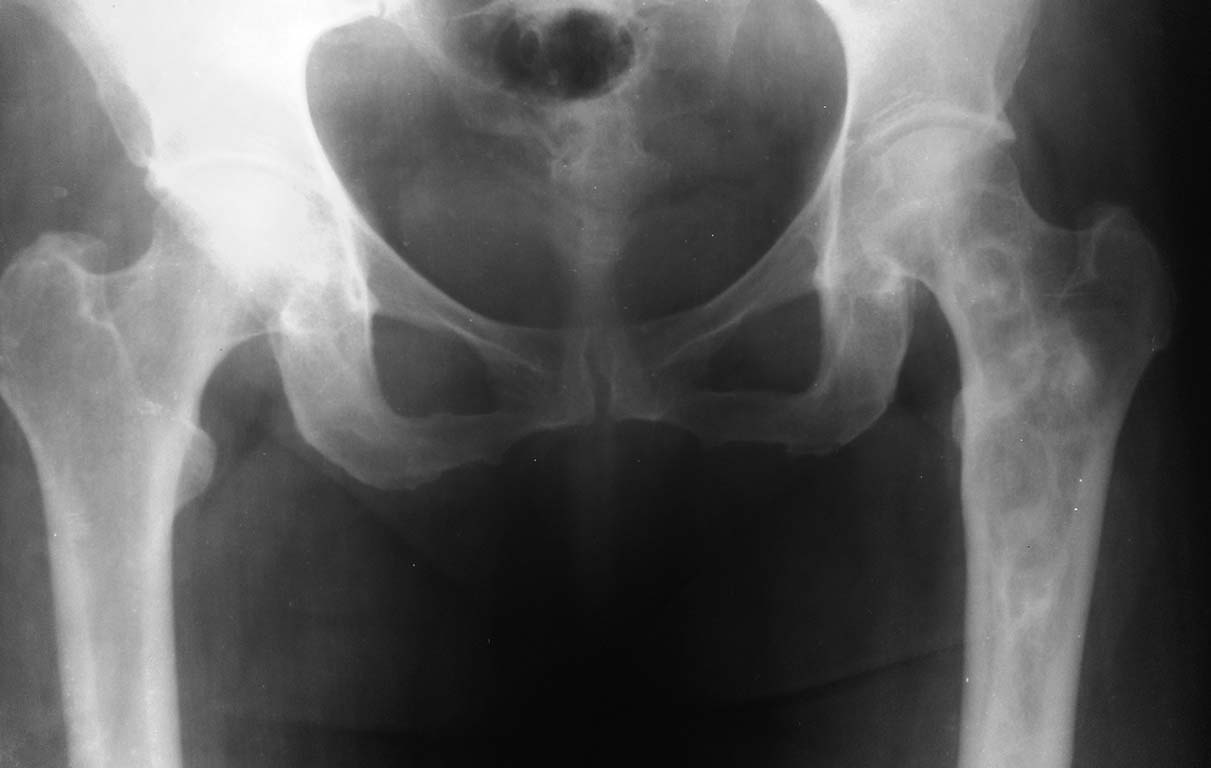

Фиброзная дисплазия проксимального отдела бедренной кости.

Пациентка 1952 г.р. (61 г.), поступила с жалобами на непостоянные боли в области левого тазобедренного сустава, верхней трети бедра и суставов конечностей.

Anamnesis morbi: Со слов пациентки болеет в течении 2,5лет, когда появились боли в бедре и крупных суставах. Об-но: по внутренним органам без особенностей. Пальпаторно отмечается болезненность в проекции верхней – средней трети левой бедренной кости.

04.09.13г 1-м этапом произведена: Операционная биопсия из проксимального отдела левой бедренной кости. Заключение патолого - гистологического исследования: Дегенеративное поражение костной ткани с замещением незрелой фиброзной тканью. В анализах в пределах нормы.

Планируем:

Резекцию проксимального отдела левой бедренной кости.

Тотальное цементное эндопротезирование левого тазобедренного сустава модульным имплантом.

Хотелось бы услышать Ваше мнение по тактике и методам оперативного лечения.